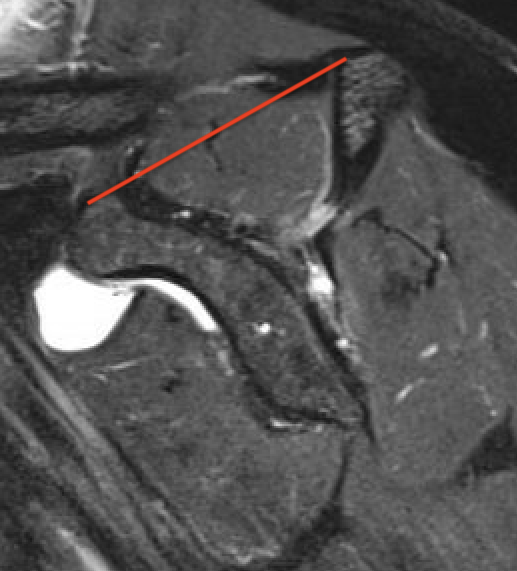

Supraspinatus atrophy

Tangent sign

- sagittal MRI

- line connecting superior coracoid and superior border scapular spine

- if supraspinatus muscle is below line, there is significant atrophy

- positive tangent sign / significant atrophy associated with larger tears / irrepairable tears

Negative tangent / no atrophy Positive tangent / significant supraspinatus atrophy